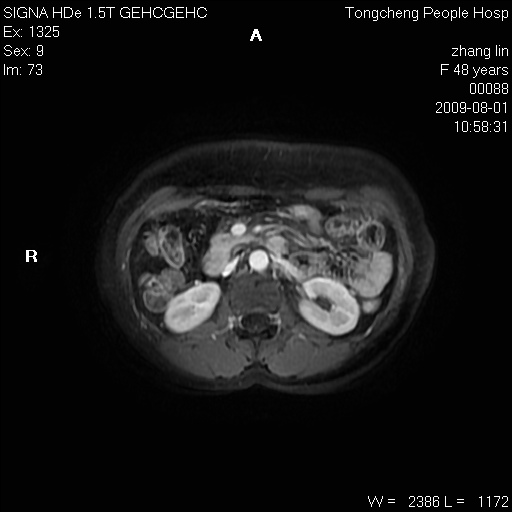

女,48岁。健康体检,彩超发现右肾占位性病变。平素健康。

临床诊断:右肾占位性病变,性质待定(囊肿?肿瘤?)。

上中腹部mr平扫+增强扫描,图像如下:

右肾上极见一类圆形病灶,t1wi呈等信号t2wi呈等高混杂信号,三期增强无强化,边界清---考虑囊肿出血。

同反相位均表现为等信号,病变无强化,考虑含蛋白的囊肿可能,弥散加权相或许有些帮助,